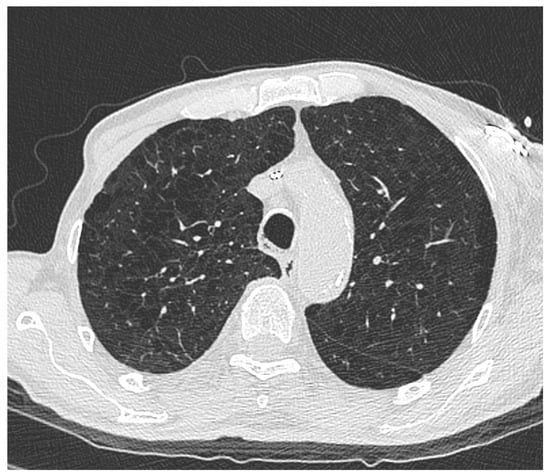

2.3. Imaging Analysis